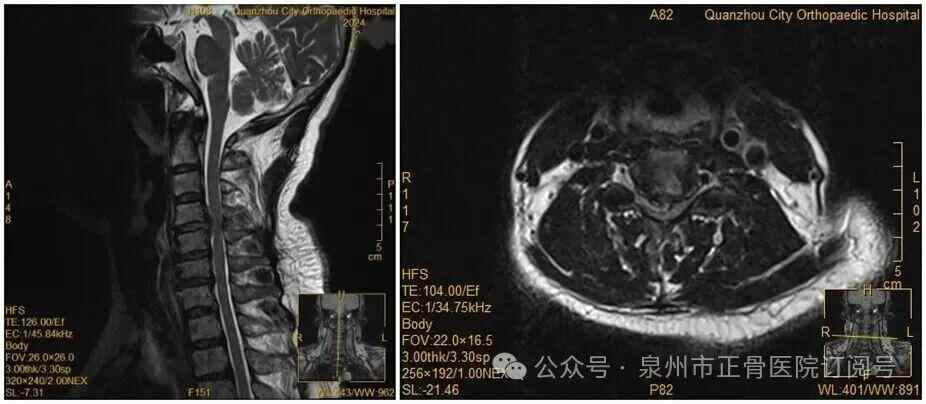

近日,福建泉州50多岁的王女士遭遇了一场“突如其来的灾难”。女士回头。晚上,王先生拿起手机。突然,他的上肢瘫痪了,再也没有举起双手的力气。过去,她因双手麻木疼痛到医院就诊,被诊断为颈椎间盘突出症。脊柱二科主治医师杨升平回忆:“会诊时,我们明确告知患者,她的颈椎间盘突出严重,符合手术指征,建议尽快手术。但她坚持保守治疗。”没想到,就诊当晚,王女士正要拿起手机时,却突然双手失去知觉——主要肌力降至1级或0级,诊断为瘫痪。 “假设转弯时,“脱出的椎间盘突然压迫脊椎神经,造成慢性症状。”医生说。虽然王女士术前核磁共振显示瘫痪,但王女士还是很害怕。王女士在手术中,不愿意接受手术。经过患者的解释以及医疗团队和王女士家属的鼓励,王女士已经准备好了。王女士接受了手术。医院对王女士进行了紧急手术。手术很顺利,经过一段时间的恢复,他的腿已经好了。医生提醒,这种常见的颈椎问题,严重时可能会导致瘫痪的风险,所以当出现颈部僵硬、上肢疼痛等疑似症状时,应尽快就医。